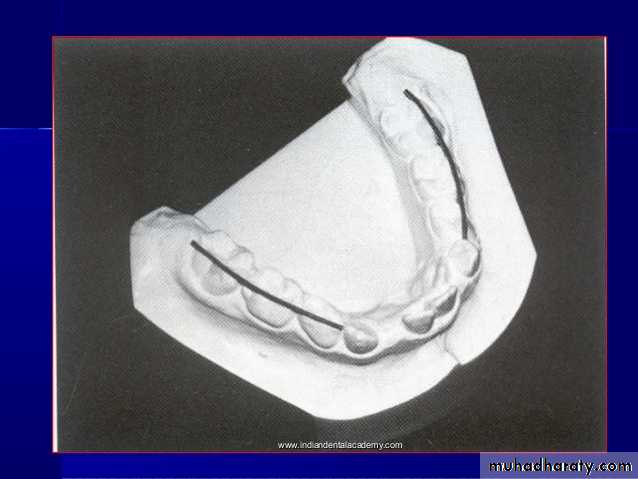

1-Symmetry

A transparent ruled grid is the simplest tool to use to establish symmetry. When it is placed over the maxillary cast and lined up with the midpalatal raphe, any distortion of arch form and shifts of dental units can be determined quickly

• Model AnalysisWidth evaluation

Arch width can be divided into three parts:

The preceding width (inter-canine width)

Middle arch width (first premolar width of the central inter-nest)

Posterior segment arch width (the first permanent molars between the width of the central nest)

the preceding width

Middle arch widthPosterior segment arch width